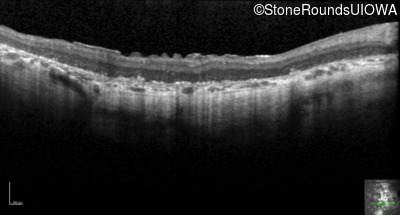

Optical Coherence Tomography - Left - Light Perception

Exemplar / OCT Stack